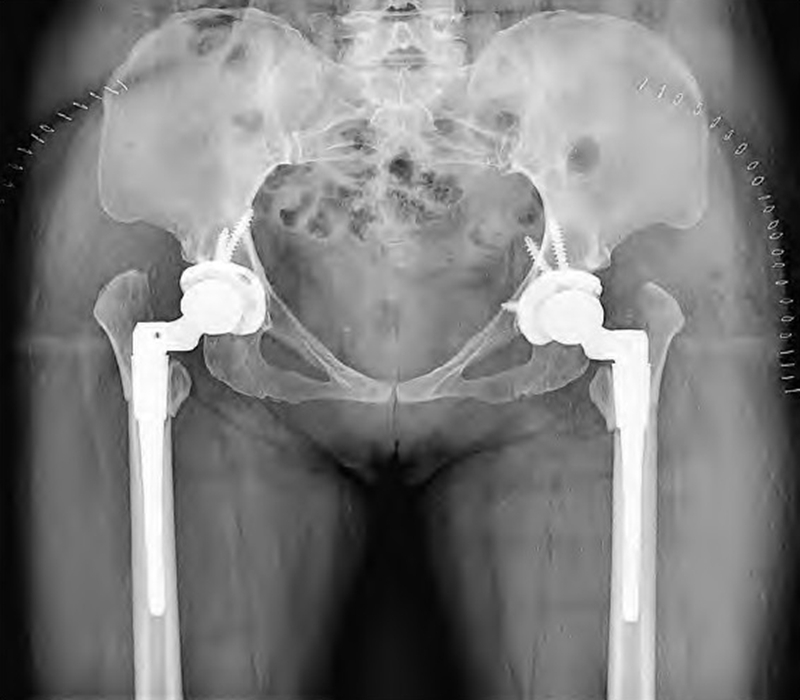

髋臼重建目前共识是髋旋转中心的正常化,即将髋臼杯放置在真臼或接近真臼位置(图4)。真臼前后柱骨质丰厚、骨小梁方向多向,臼杯植入后骨性覆盖充分稳定性好;若置于假臼,髂骨翼薄不能充分固定,并且杠杆力臂高于正常,导致髋关节负荷过大假体松动率高,并且外展肌功能不全导致跛行。

图4 双侧THA术后DR:双侧臼杯均建立在真臼位置,假体适度内移,未额外骨移植,双侧均应用44mm生物型多孔臼杯和高交联聚乙烯内衬,搭配28mm陶瓷股骨头假体。股骨侧采用可调节前倾角的组配式假体,近端和远端均获得良好固定,双侧均采用转子下斜行截骨方式,截骨处固定可靠,未加用额外固定方式,假体匹配良好,双下肢基本等长

Hartofilakidis等倾向股骨近端截骨,因为可直接纠正后置的大转子,但截骨后的大转子片段放置在皮质骨上愈合困难;残留股骨干通常不适合生物型假体,须用小号骨水泥股骨柄;如果截骨距离向下达到小转子水平,髂腰肌肌腱必须松解,可能影响髋关节屈曲力。因此,虽然目前尚无客观数据支持某一截骨方式,但多数研究倾向转子下截骨,其愈合率超过80%。转子下截骨可保留干骺端区域,提供股骨柄大部分旋转稳定性,恢复外展肌力臂并允许同时矫正内外翻和前倾畸形并允许在术中调整截骨长度。转子下横行截骨操作较容易,但截骨处接触面积小,假体远端旋转稳定性欠佳,可能出现截骨处失稳,影响截骨愈合。而“Z”字形截骨虽可提供较大的骨接触和旋转稳定性,但技术难度较大。因此,建议选择转子下斜行截骨(图4),其中45°斜行截骨更为合理,抬高或劈开一小段股外侧肌到达转子下区域,截骨位置距离大转子尖端10cm或小转子下2cm,同时具有横行截骨的操作简单以及“Z”字形截骨的增加截骨处的接触面积、具有防旋功能、利于截骨愈合等优点。